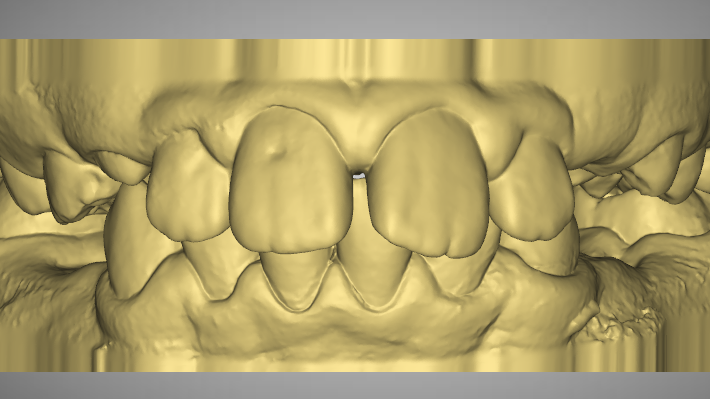

Pre-Op Analysis – 2020-11-25

- Class 2 div I and div II

- Lower lip entrapment

- Yellow Stone Model = Pre-Op at 2020

- Blue Overlay = Progress scan at 2022-07-04 after about 12 months of Mybrace K1 which came after 6 months in aligners.